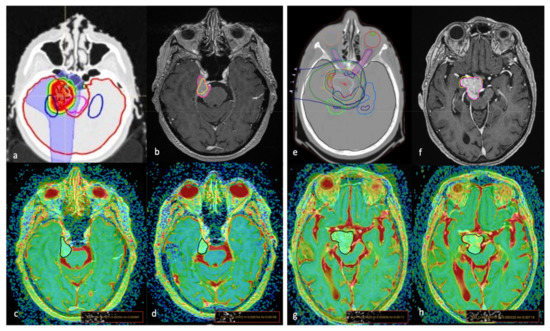

2. Materials and Methods

2.2. MR Imaging Techniques

2.3. Imaging Analysis